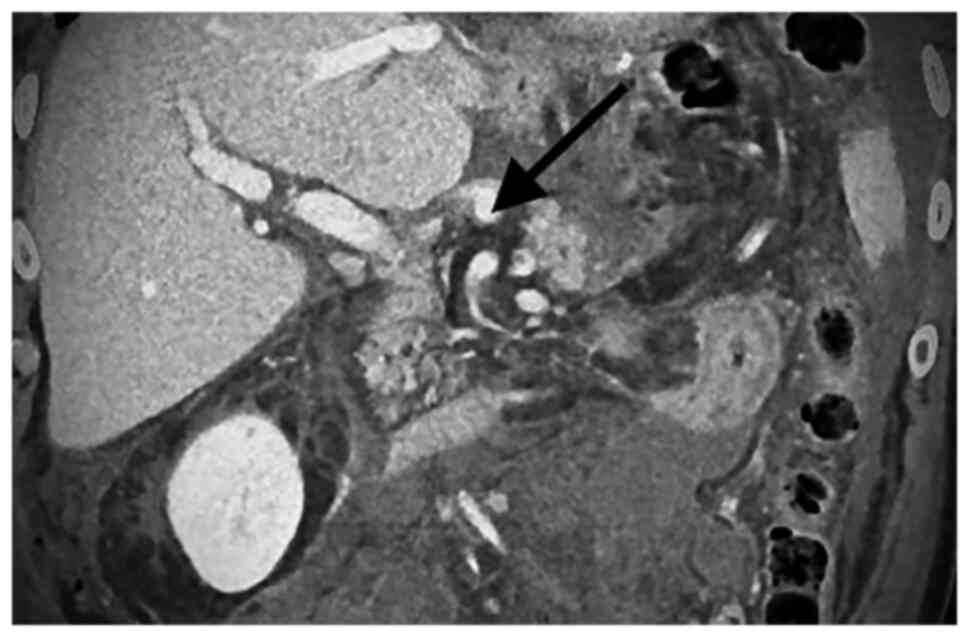

Visceral artery aneurysms are defined in this retrospective analysis as a true aneurysm in the celiac trunk (CT), superior mesenteric artery (SMA), inferior mesenteric artery, and/or their branches. Visceral artery aneurysms (VAAs) are rare and mostly asymptomatic., Rapid growth, size >2 cm, and pregnancy are risk factors associated with rupture. True visceral aneurysms are aneurysms are the result of weakening and thinning of the artery wall. Atherosclerosis, connective tissue disorders, infection (for example pancreatitis) and abdominal surgery are known risk factors for the development of VAA. Nowadays, conservative therapy, endovascular, and open surgery are the treatment options for patients with visceral aneurysms (VAA). During the last decade, endovascular repair of VAAs has been increasingly used (1-6). Catheter-based embolization or stent-graft placement are two major treatment options. Most VAAs originate from the splenic artery (SA) (60%) (Figs. 1 and 2), followed by the hepatic artery (HA) (20-50%) (Figs. 3 and 4). An origin from the superior mesenteric artery (SMA) (6%) (Figs. 5 and 6), the celiac trunk (CT) (4%) or other, smaller visceral arteries is considerably less common (7).

There were eight patients with an aneurysm of the SA, two patients with aneurysms of the SMA, one patient with an aneurysm of the HA and one patient with an aneurysm of the CT. Only one patient was symptomatic and presented with signs of bleeding. All patients received a contrast-enhanced CT-scan.

The median aneurysm diameter was 2 cm (range 1.5 cm to 5 cm) for all aneurysms, 3.75 cm for aneurysms of the SMA, 2 cm for aneurysms of the SA and for aneurysms of the CT and 1.5 for the aneurysm of the HA.